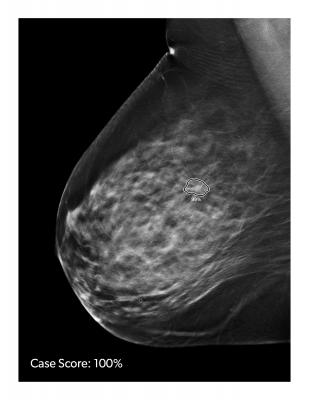

In addition, new data presented by Mark Traill, M.D., at the NCoBC Interdisciplinary Breast Center Conference highlights the comparison of ProFound AI Case Scores to BI-RADS assessment categories determined by a single radiologist without using AI in a retrospective analysis. Researchers used ProFound AI on 890 consecutive DBT studies and 50 consecutive cases with biopsy-proven breast cancer detected with DBT. Results showed a strong positive correlation between a ProFound AI Case Score of less than 60 percent and patients assessed as likely to be normal (BI-RADS 1 or 2), while most of the biopsy-proven cancers had a Case Score of greater than 60 percent.

“We wanted to describe the Case Score distribution in a screening population to better understand the significance of score value as a clinical decision tool,” said Traill. “We found a very strong correlation between a Case Score of less than 60 percent and a BI-RADS score assessment of 1 or 2. Also, only 15 percent of the Case Scores were greater than 60 percent, but this group contained most of the detected cancers. As a clinical decision tool, a Case Score above 60 percent is an independent indicator of higher chance of underlying malignancy. This is very helpful in guiding the intensity of the cancer search, while improving workflow functionality and reducing stress for the reading radiologist.”

ProFound AI for DBT is a high-performance, deep-learning workflow solution trained to detect malignant soft-tissue densities and calcifications. It became the first 3D tomosynthesis software using artificial intelligence (AI) to be FDA cleared in December 2018. Built with the latest in deep-learning technology, ProFound AI for DBT rapidly analyzes each tomosynthesis image, detecting malignant soft tissue densities. Certainty of Finding and Case Scores are relative scores computed by the ProFound AI algorithm and represent its confidence that a detection or case is malignant. The Certainty of Finding scores help radiologists by aiding in clinical decision making. Case Scores, which are assigned to each case by the algorithm, help clinicians to gain a sense of case complexity, which may be useful for prioritizing the reading worklist. In a reader study published in Radiology: Artificial Intelligence, ProFound AI for DBT Version 2.0 was clinically proven to reduce reading time for radiologists by 52.7 percent, improve radiologists’ sensitivity by 8 percent, and reduce the rate of false positives and unnecessary patient recalls by 7.2 percent.